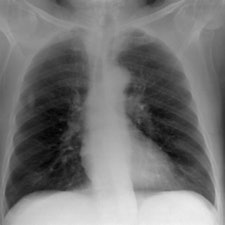

They tested the model in a "virtual clinical trial" in which four experienced image evaluators graded images of average and obese adult patients at different potentials, receptor doses, and scatter rejection techniques on an Agfa HealthCare CR system using MD-4.0 phosphor plates. The quality of the images was evaluated using visually graded analysis. The researchers also assessed the influence of rib contrast.

For average-sized patients, image quality improved when tube potential was reduced compared with the reference (102 kVp) and no scatter rejection was indicated. For obese patients, it has been shown that an antiscatter grid is indicated and should be used in conjunction with as low a tube potential as possible (while allowing exposure times, 20 msec), the researchers wrote. It is also possible to reduce receptor air kerma by 50% without adversely influencing image quality. They also found rib contrast did not interfere at any tube potential.

In 50 average patients who were reconstructed without scatter rejection, readers gave higher marks for images acquired with lower tube potential (kVp) settings, demonstrating that image quality improves with lower kVp, the researchers said. Visual grading analysis system scores ranged from 0.41 for 50 kVp to 0.03 for 109 kVp, but there was very little difference between image quality at tube potentials greater than 102 kVp (0.03 at 109 kVp to 0.07 at 150 kVp), according to the authors.